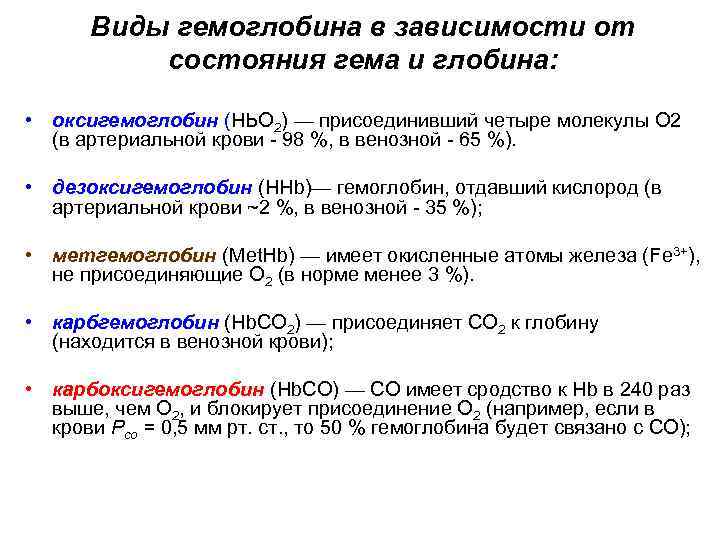

Виды гемоглобина в зависимости от состояния гема и глобина: • оксигемоглобин (НЬО 2) — присоединивший четыре молекулы О 2 (в артериальной крови - 98 %, в венозной - 65 %). • дезоксигемоглобин (ННb)— гемоглобин, отдавший кислород (в артериальной крови ~2 %, в венозной - 35 %); • метгемоглобин (Met. Hb) — имеет окисленные атомы железа (Fe 3+), не присоединяющие О 2 (в норме менее 3 %). • карбгемоглобин (Нb. СО 2) — присоединяет СО 2 к глобину (находится в венозной крови); • карбоксигемоглобин (Нb. СО) — СО имеет сродство к Нb в 240 раз выше, чем О 2, и блокирует присоединение О 2 (например, если в крови Рсо = 0, 5 мм рт. ст. , то 50 % гемоглобина будет связано с СО);

Виды гемоглобина в зависимости от состояния гема и глобина: • оксигемоглобин (НЬО 2) — присоединивший четыре молекулы О 2 (в артериальной крови - 98 %, в венозной - 65 %). • дезоксигемоглобин (ННb)— гемоглобин, отдавший кислород (в артериальной крови ~2 %, в венозной - 35 %); • метгемоглобин (Met. Hb) — имеет окисленные атомы железа (Fe 3+), не присоединяющие О 2 (в норме менее 3 %). • карбгемоглобин (Нb. СО 2) — присоединяет СО 2 к глобину (находится в венозной крови); • карбоксигемоглобин (Нb. СО) — СО имеет сродство к Нb в 240 раз выше, чем О 2, и блокирует присоединение О 2 (например, если в крови Рсо = 0, 5 мм рт. ст. , то 50 % гемоглобина будет связано с СО);